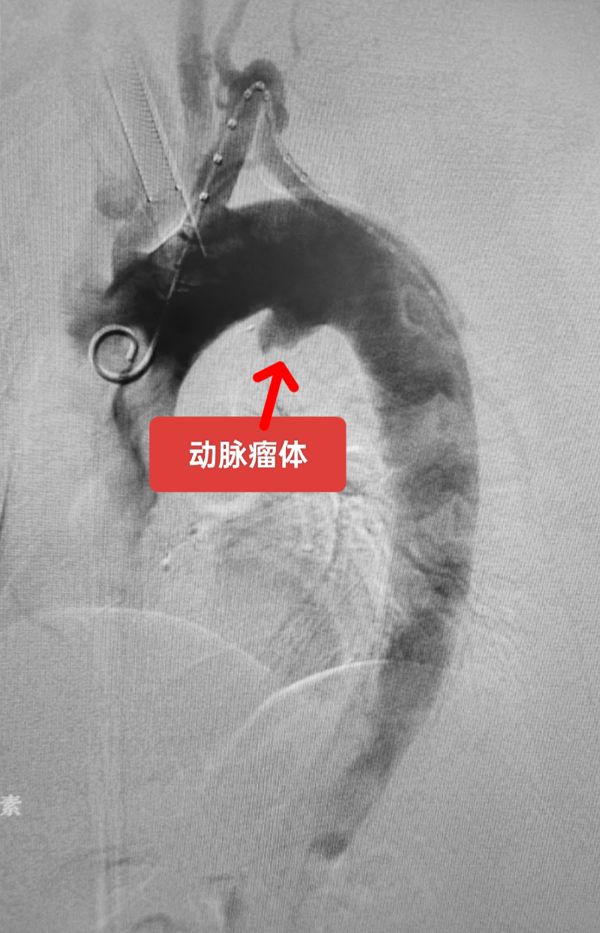

该男性患者因胸部不适入住我院,CTA发现胸主动脉弓降部小弯侧动脉瘤外突明显,随时有破裂风险危及生命。经多学科会诊后根据动脉瘤部位,精准测量后决定实施体外开窗手术方案。